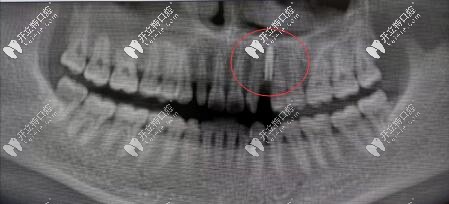

牙齒隱裂拔掉做了價(jià)格適中的法國anthogyr種植體,30+就擁有了人生第1顆假牙。

案例:法國安卓健Axiom?2.8mm型號種植體修復(fù)缺失切牙虎牙超贊

中切牙側(cè)切牙缺失,牙間距過小怎么種牙?長沙美奧口腔法國安卓健Axiom? 2.8mm種植體修復(fù)缺失虎牙案例賞析。